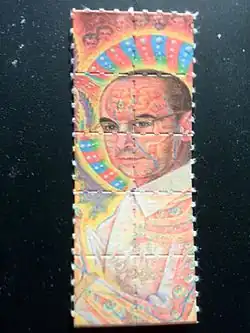

-

-

-

-

Mescalinhaltiger Kaktus (Peyote) -

DOB-Blotter

DOB-Blotter